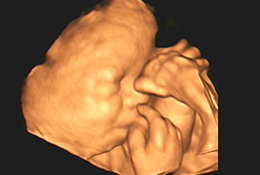

Com alta tecnologia realizamos diversos tipos de ultrassonografias: Obstétrica, Obstétrica com Doppler, Morfológica, 4D, Transvaginal, Transvaginal para pesquisa de Endometriose, Abdominal, Mamas, Tireoide e outros.